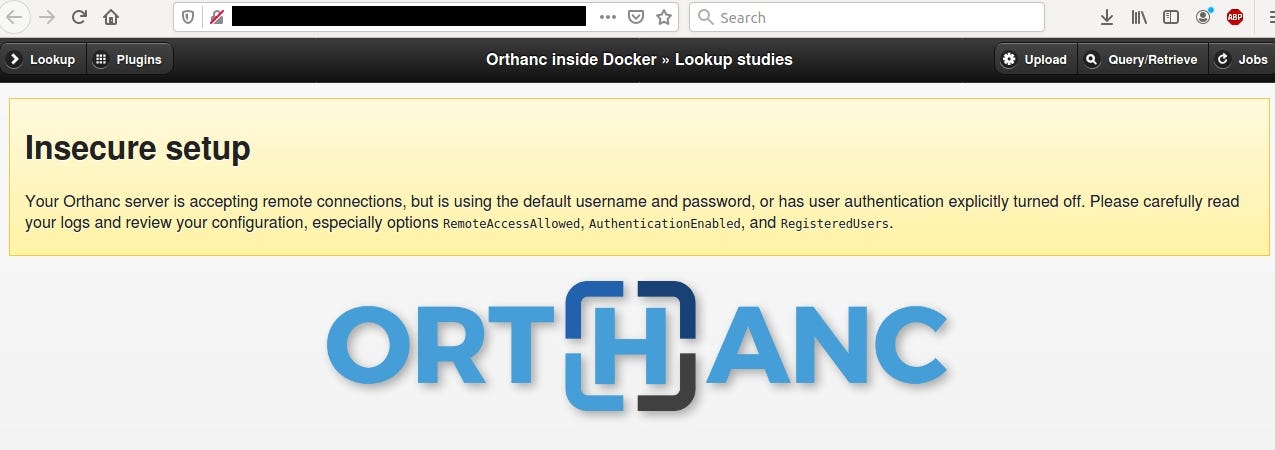

Orthanc Explorer

It’s yet another DICOM viewer software. It allows to check patient’s X-Ray scans and other medical info. A lot of Orthanc instances are open without any authentication.

It’s all fun and games until some script kiddies start to test it without proper authorization.

If you want to test functionality and GUI of this software, you can check out demo that’s publicly accessible.

https://demo.orthanc-server.com/app/explorer.html